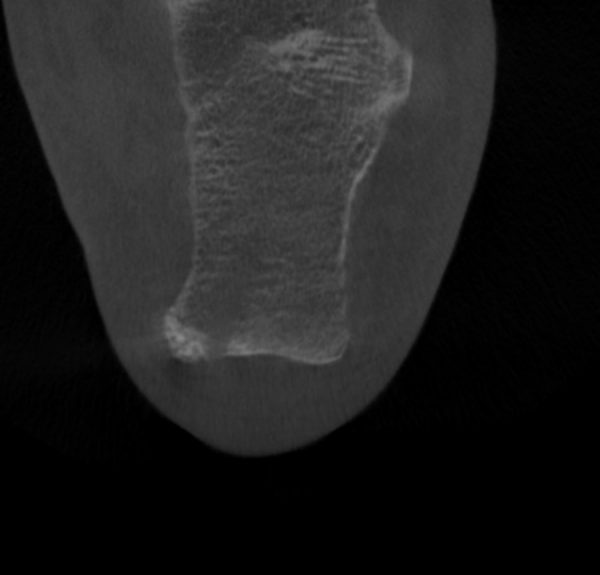

Home Schwerpunkte Krankheitsbilder Haglund-Syndrom & Haglundferse Haglund Syndrom und hinterer Fersensporn post OP

Haglund Syndrom und hinterer Fersensporn post OP